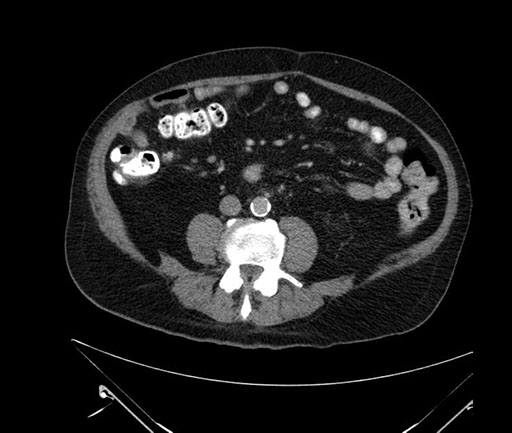

Axial - stented

Coronal - stented